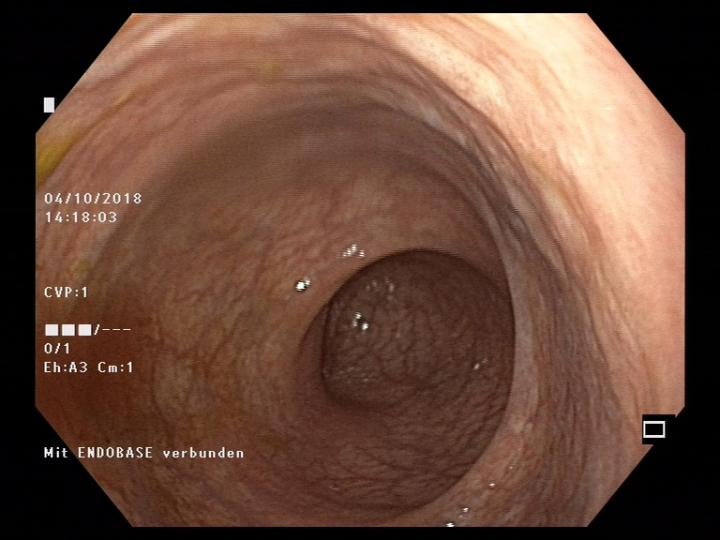

Healthy Colon

image: This is an endoscopical picture of a healthy colon mucosa. view more

Credit: Pascal Juillerat, University of Bern